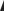

75岁男性,主诉进行性加重的步态障碍和四肢痛性感觉异常1年。既往史包括高血压和中度血友病甲。查体提示痉挛性四肢轻瘫伴括约肌功能障碍,下肢行走数米即感到无力。无感觉平面。颅神经检查阴性。结合6月前的影像学,临床诊断为颈髓病,但确切病因尚不知晓。脊髓MRI提示广泛弥漫的颈髓肿胀(图1)。头颅MRI正常。行影像学检查前患者未服用任何糖皮质激素。

(图1:A:矢状位T2WI;B:矢状位T1WI;C:矢状位T1增强)